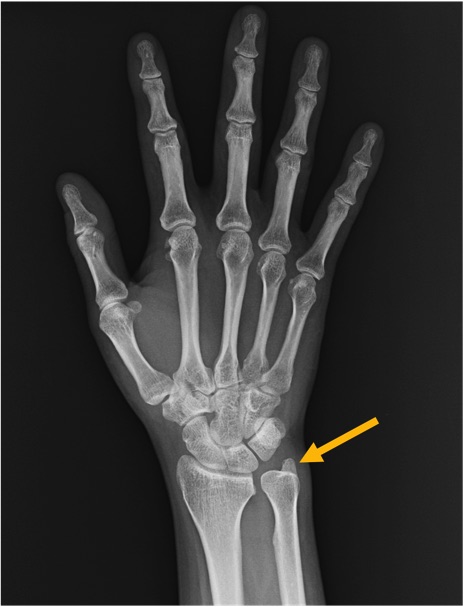

尺骨茎状突起(ulnar styloid process)の手関節レントゲン画像における正常解剖

尺骨(ulna)